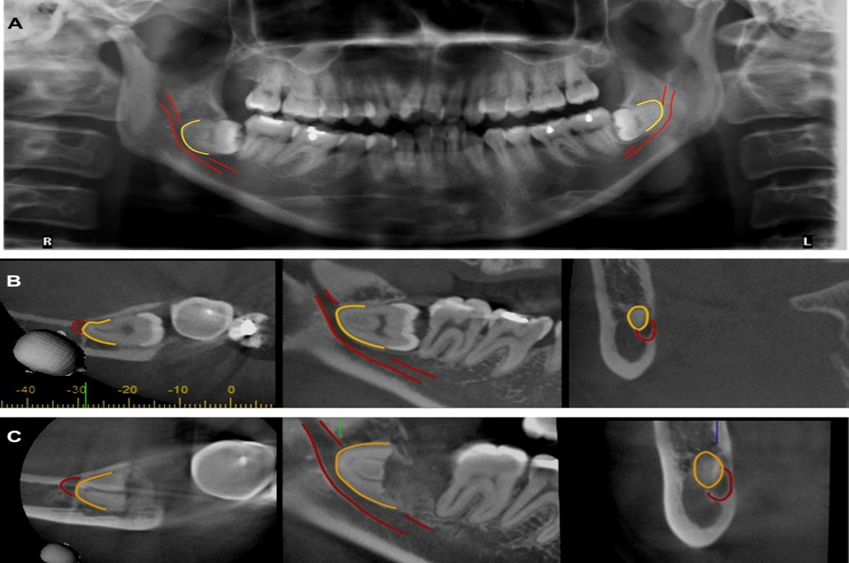

| - CBCT trong chẩn đoán răng khôn mọc lệch/ mọc ngầm: Nhờ có sự giúp đỡ của CBCT, bác sĩ có thể lường trước được mối liên quan của dây thần kinh với chân răng khôn cũng như quyết định thực hiện kỹ thuật nhổ răng khôn trong một lần duy nhất hay chỉ cắt thân răng khôn, chờ chân răng trồi lên. | | |

Hàng năm, có rất nhiều bệnh nhân đến thăm khám và được tư vấn chụp Cone Beam CT tại Bệnh viện đa khoa tỉnh Quảng Trị đem lại kết quả điều trị thành công cao. Dưới đây là một vài trường hợp bệnh nhân cụ thể điều trị tại Khoa Răng Hàm Mặt: - Trường hợp 1: Bệnh nhân nữ, 33 tuổi đến khám với lý do đau nhức vùng răng 38, 48 nhiều lần. Thăm khám trên lâm sàng, răng 38, 48 lệch gần, nhú 1 phần thân răng trên cung hàm, nướu tương ứng sưng đỏ. Bệnh nhân được chụp XQ răng toàn cảnh thường qui nghi ngờ có nguy cơ cao chèn ép ống thần kinh hàm dưới, gây nguy cơ chấn thương thần kinh cao khi phẫu thuật nhổ răng khôn. Bệnh nhân được chỉ định chụp Cone Beam CT kiểm tra, qua các lớp cắt đã thấy rõ hình ảnh răng khôn hàm dưới mọc lệch chèn ép thần kinh .